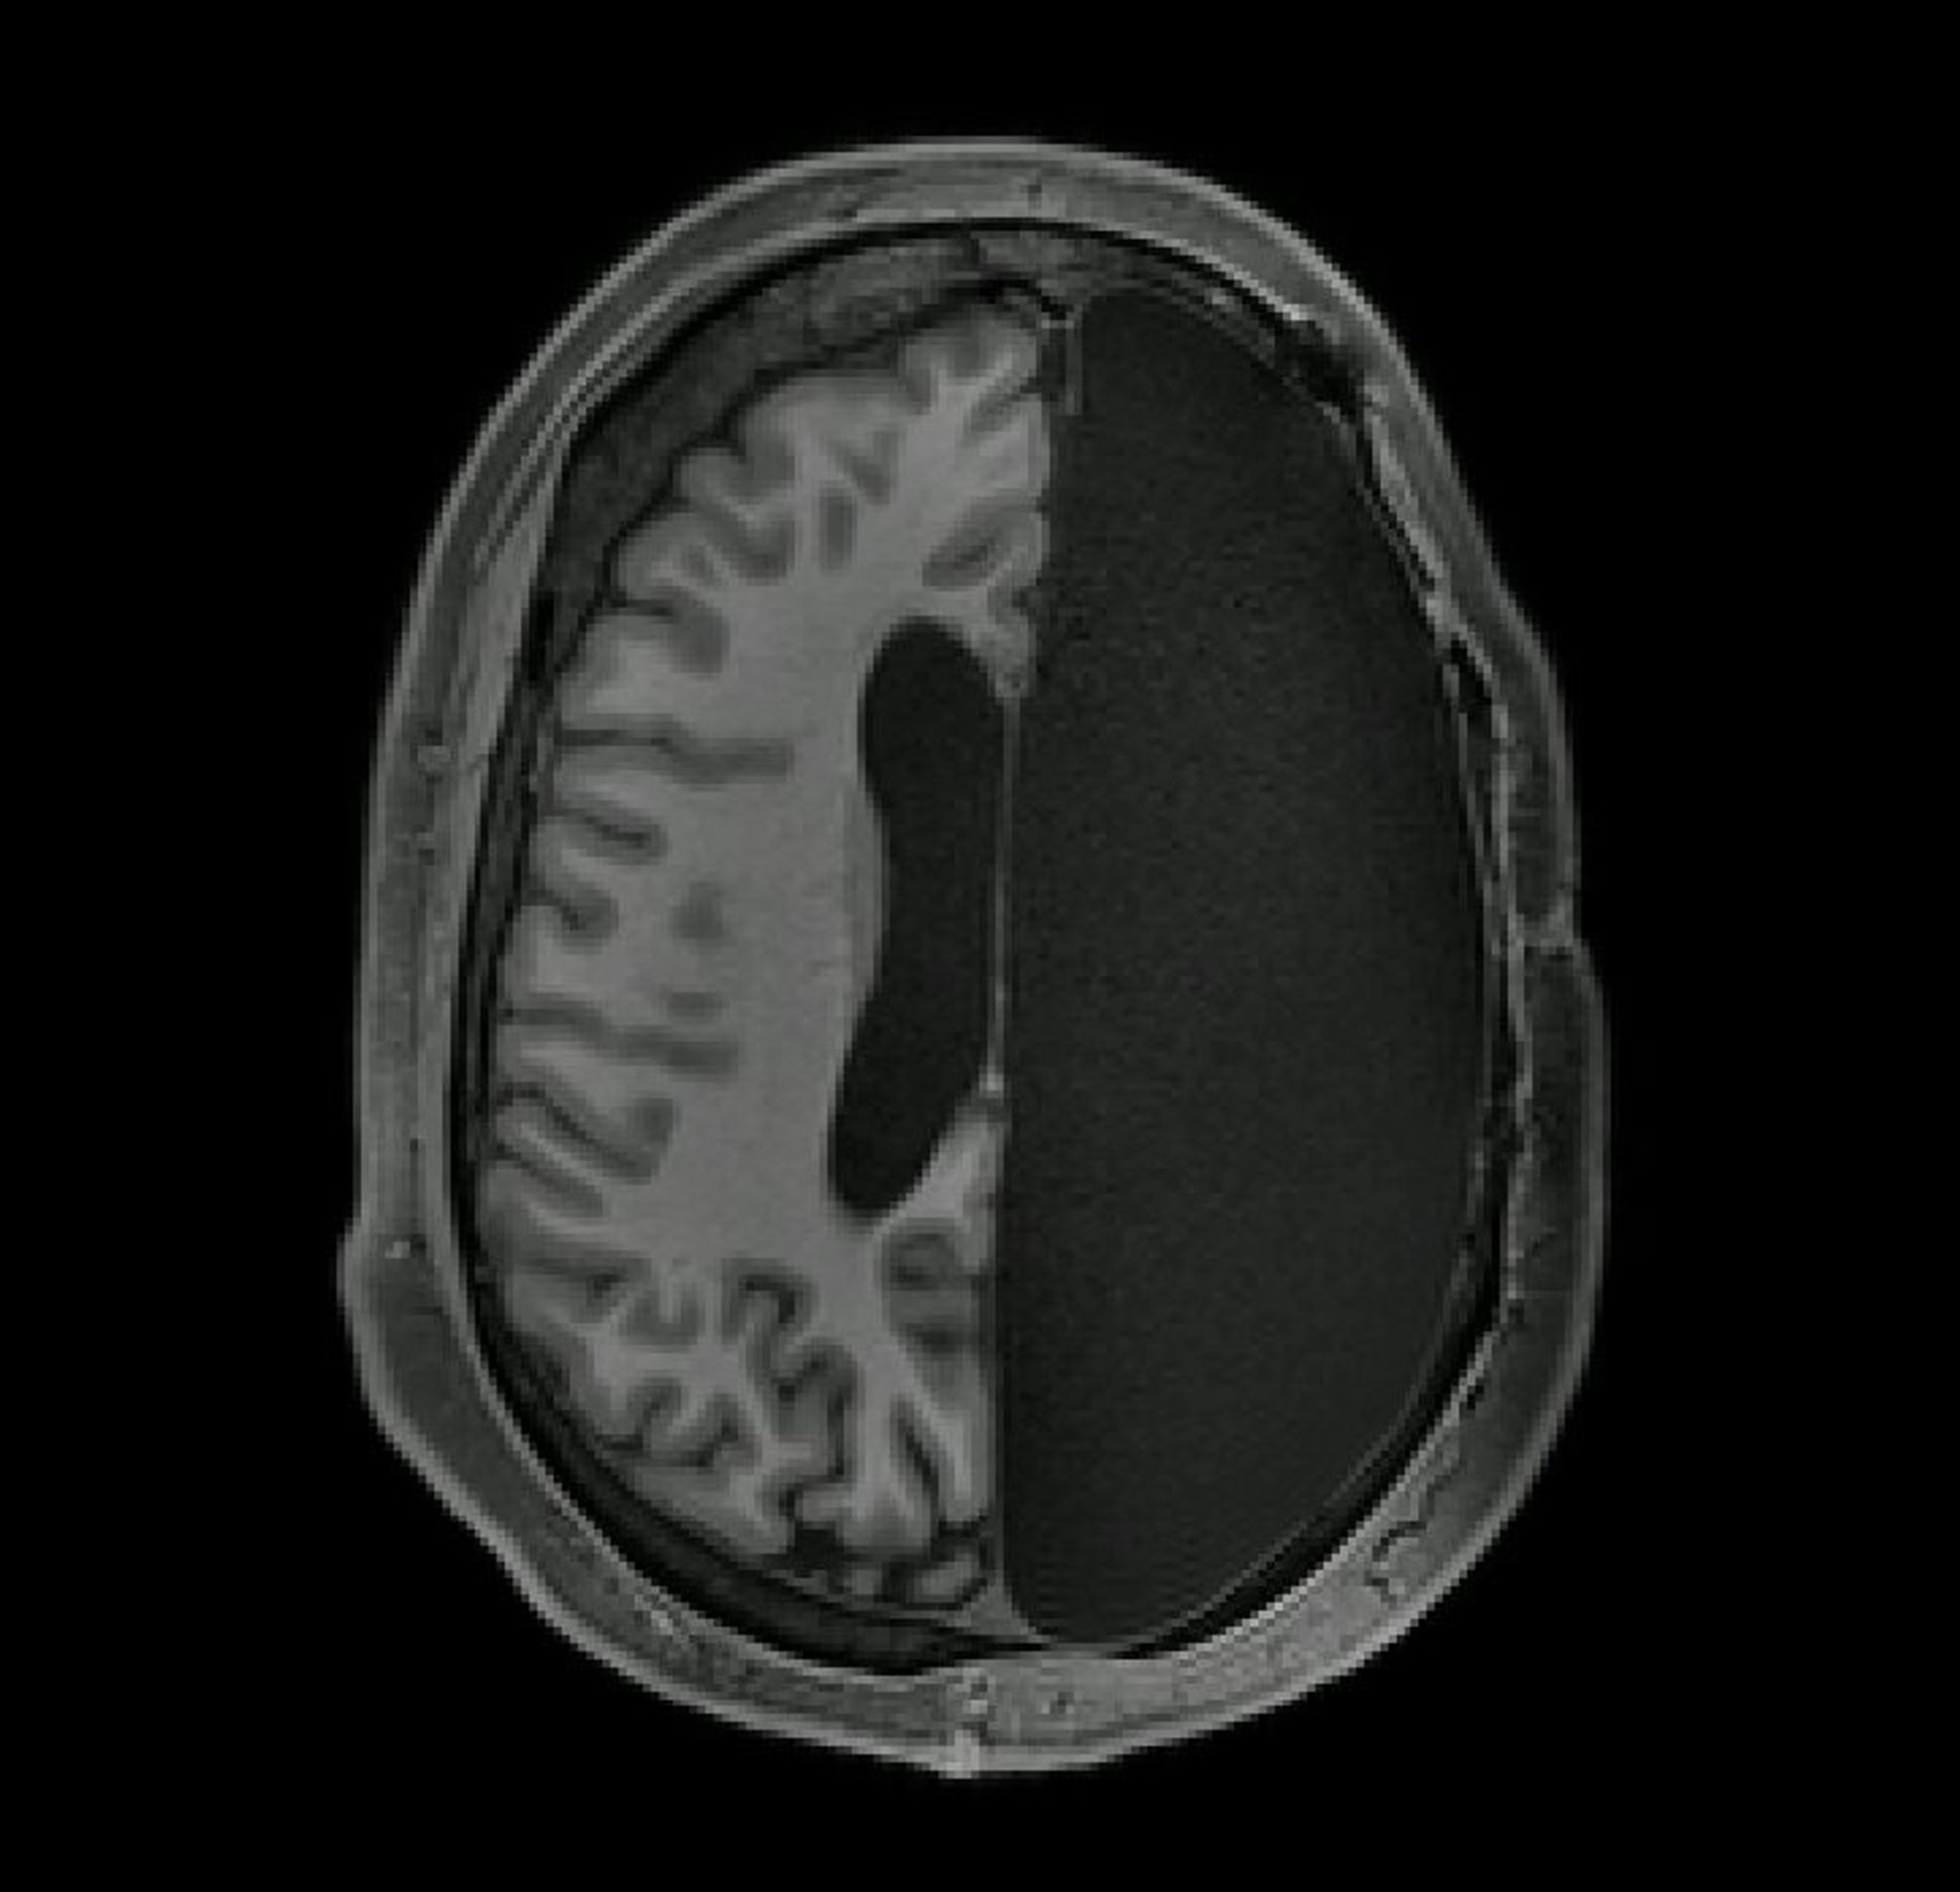

Fjerning av en cerebral hemisfære er en ekstremt sjelden prosedyre. Det utføres kun på epileptiske barn som ikke har respondert på annen behandling. Hvis medisiner eller mindre invasive prosedyrer ikke hjelper og anfallene i seg selv er svært farlige og skadelige for barnets utvikling, er det noen ganger ikke noe annet valg enn å fjerne eller koble fra en hjernehalvdel der epilepsien har spredt seg.

Høres det ut som en forferdelig lyte på sykehistorien? Nei, dette er et helt normalt, men svært sjeldent kirurgisk inngrep som har en suksessrate på 85-90 %. pasientene. Dette er selvfølgelig en kardinal behandlingsmetode, men tenk ikke at folk med en halv hjerne ikke kan leve fullt ut.

Fjerning av halvkulen utføres bare i ekstreme tilfeller. Som et resultat forbedres de mentale evnene til disse barna selv etter intervensjonen, fordi de voldsomme og konstante anfallene forstyrret deres utvikling. I 1975 studerte forskere flere mennesker som vokste opp med bare halvparten av hjernen. En gutt som mistet halvkulen i en alder av fem vokste opp, ble uteksaminert fra college, tok en mastergrad og ble mer vellykket enn jevnaldrende. Selvfølgelig er ikke alle like heldige. Andre mennesker er preget av nedsatt kognitiv utvikling, med talevansker (på grunn av skadede talesentre), men de fleste lever normale liv.

Og det de så var en spesiell evne til hjernen til å tilpasse seg. Forskere observerte at personer som fikk fjernet en del av hjernen hadde betydelig sterkere forbindelser mellom ulike hjerneregioner. Disse deltakerne gjennomgikk hemisfærektomi i tidlig barndom, noen så unge som 3 måneder gamle og de eldste ved 11 år. I barndommen er hjernen ekstremt plastisk, den danner lett nevronale forbindelser. Dermed kompenserte hjernen raskt for den manglende halvkulen ved å etablere sterkere forbindelser med de overlevende hjerneområdene.